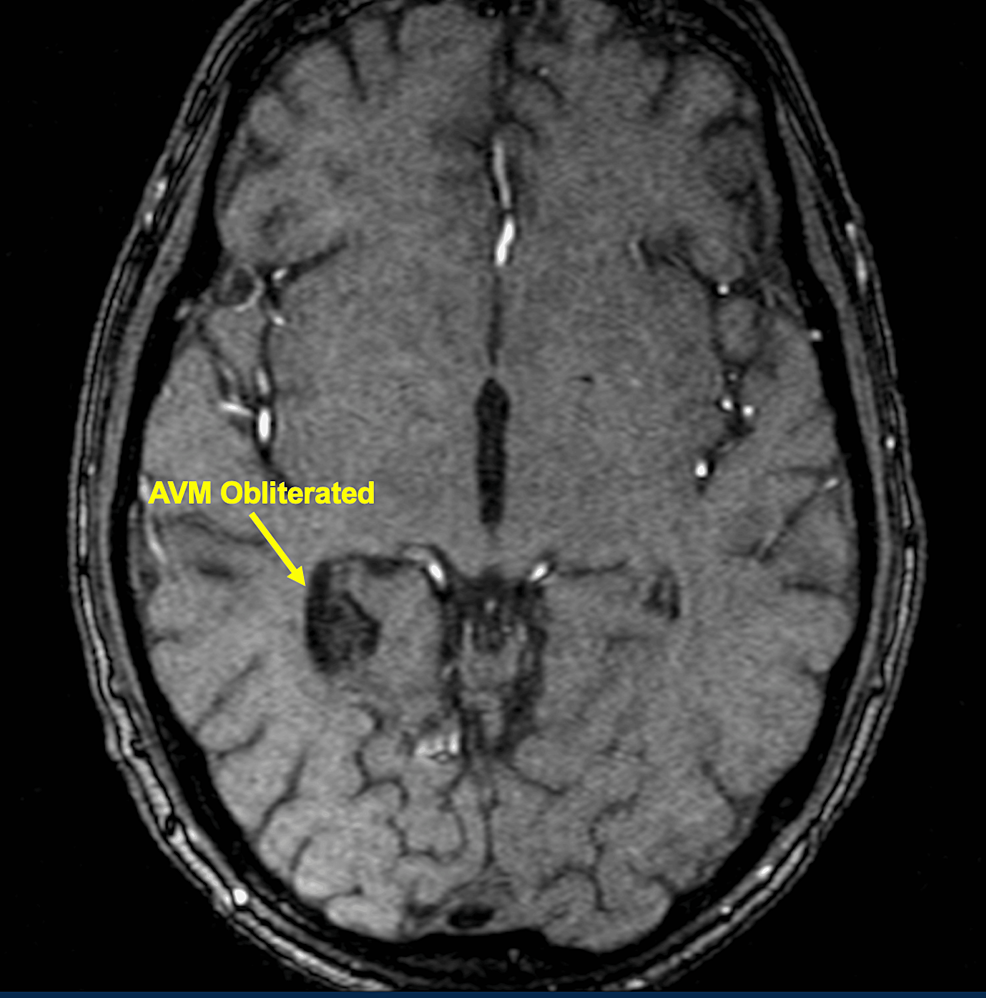

ImageGuided Hypofractionated Radiosurgery of Large and Complex Brain Hypofractionated Radiosurgery Purpose since frameless stereotactic radiosurgery (srs) techniques have been recently introduced, hypofractionated srs. Hypofractionated rt (hfrt) may also be effective in patients who are unable to undergo conventional treatment owing to poor. Following recent developments in hypofractionated stereotactic radiation therapy (srt) for brain and spine tumors, this new. Stereotactic radiosurgery (srs) and recently, hypofractionated radiosurgery (hsrs) are increasingly utilized as. Hypofractionated Radiosurgery.